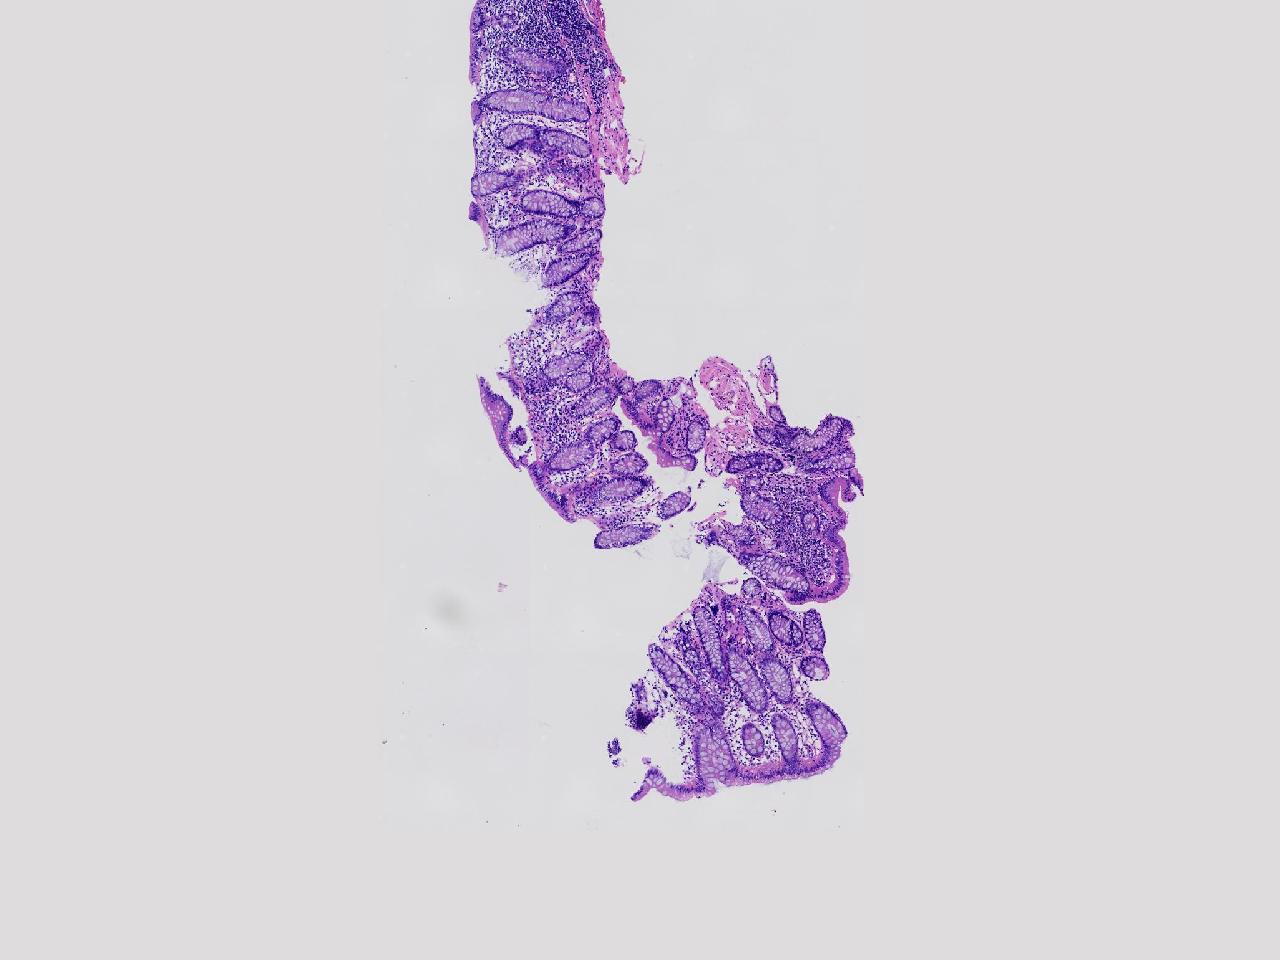

可见淋巴组织增生? 炎性?

性别

女

年龄

75岁

临床诊断

肠镜活检

一般病史

升结肠.降结肠.乙状结肠.直肠见多发直径约0.2—0.3厘米大小不等的扁平及指状隆起,表面光滑,升结肠取材1块。

标本名称

乙状结肠处活检

大体所见

灰白色不整形软组织1块。

粘膜慢性炎,局部淋巴组织增生。